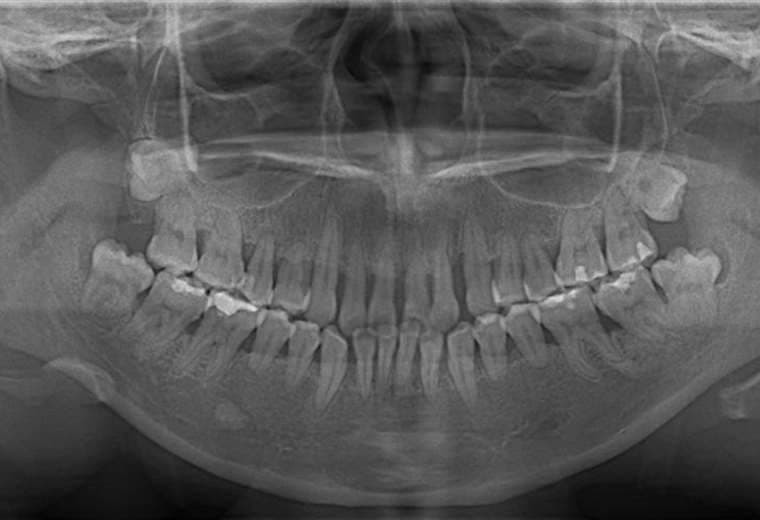

Una infección en las encías, un golpe o incluso la osteoporosis pueden provocar una pérdida del hueso dental y esta condición puede traer consecuencias que afectan la calidad de vida de quien la padece.